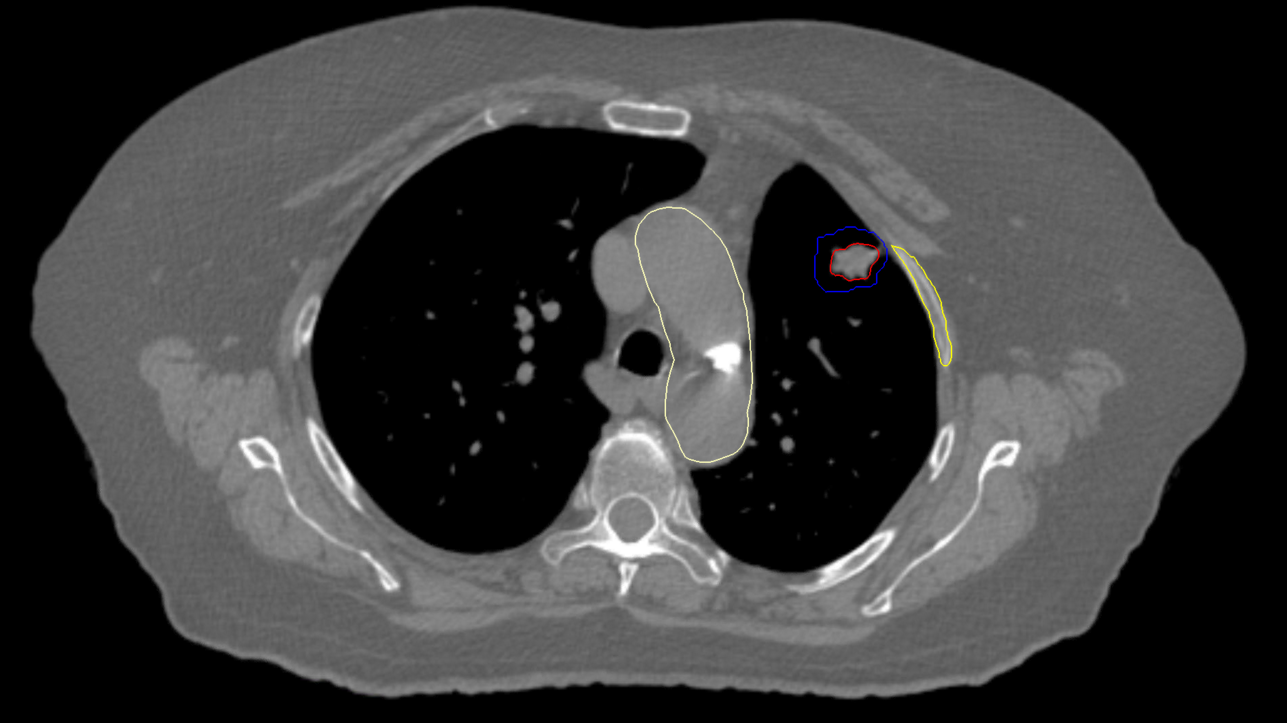

Right Central Lung Metastasis

< View All Plan Studies CYBERKNIFE SYSTEM Right Central Lung Metastasis Case History AGE: 62-year-oldGENDER: Male Medical History Chronic obstructive pulmonary disease (COPD), previous surgery on right lung Chest CT: Suspicious lesion in the right lower lobe PET-CT: hypermetabolic nodule, 3.1cm no evidence of regional or distant metastasis Non-Small Cell